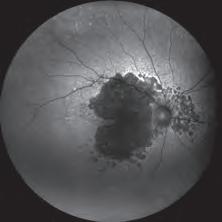

optomap®, the ONLY single-capture, 200° ultra-widefield retina image